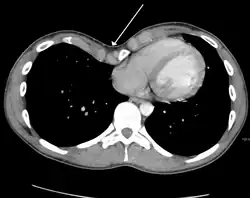

A massive left pleural effusion displacing the heart and trachea to the right

A pleural effusion is an accumulation of fluid inside the pleural space. If this collection of fluid gets large enough, it can also push structures in the chest away from it and cause a mediastinal shift. However, a pleural effusion can also pull the mediastinal structure towards itself. If this is the case, then there is an underlying condition causing the collapse of the lung on that side. An example is a tumor obstructing a bronchus and causing lung collapse and pleural effusion.[3]